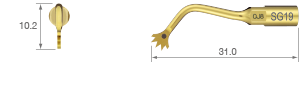

For chin bone harvests, notably for the mental foramen and mandibular ramus. For general bone surgery.

• POWER LEVEL [SURG] 100%

• TiN coating

• Dots mark 6, 8 and 10 mm from tip end

• 18 teeth ; 0.35 mm thick